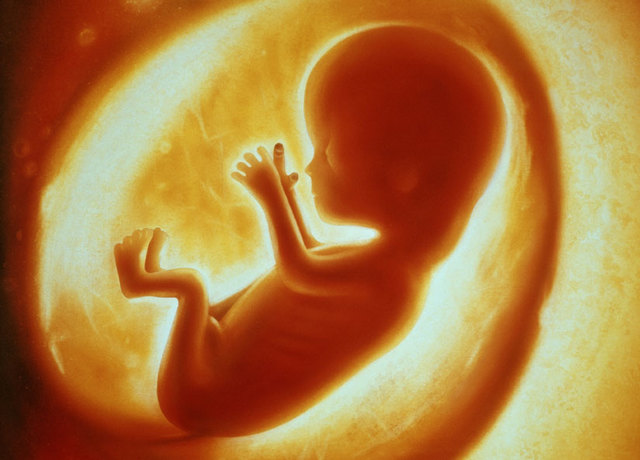

• Second Trimester (fifth month)

Second Trimester (fifth month)

Eight to twelve inches long, weighs eight ounces, sleeps and wakes at regular intervals, baby moves a lot. Mother still in golden trimester.